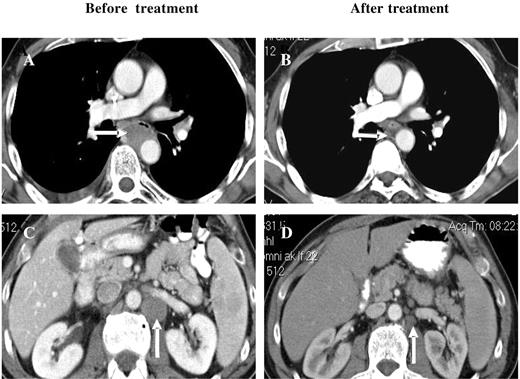

Among the other disease categories, 7 patients with NHL were enrolled, 5 were evaluable for a response, and 2 of these with B-cell NHL had PRs. One patient with relapsed/refractory peripheral T-cell NHL achieved a CR after 6 cycles of bortezomib/PegLD (Figure 3). There were also 5 patients with AML treated, 2 of whom received at least 2 cycles, whereas the other 3 experienced disease progression or progression-related toxicities that precluded further treatment. One of the 2 evaluable patients had newly diagnosed AML and was not a candidate for standard therapies. After 2 cycles he achieved a PR by the circulating blast count, which was reduced from a baseline of 7% (absolute blast count 2688) to 1% (107), though he remained transfusion dependent. This patient developed pneumonitis during cycle 3 as detailed earlier, a confirmatory bone marrow was not performed, and he did not receive additional therapy. The second AML patient had relapsed disease after multiple prior induction regimens as well as autologous peripheral blood stem cell transplantation (auto-PBSCT). An initial bone marrow showed hypercellularity with 19% blasts, which after 2 cycles became normocellular with only 4% blasts though a clonal cytogenetic abnormality persisted, and she did require intermittent platelet and red blood cell transfusions. Treatment was interrupted due to febrile neutropenia and disseminated Varicella zoster, and upon resolution of these the patient's disease had progressed. Reinitiation of bortezomib/PegLD again converted her hypercellular marrow, showing 28% involvement after 4 cycles to a normocellular marrow with 5% blasts.

Response of a patient with peripheral T-cell NHL to bortezomib and PegLD. This 64-year-old male with peripheral T-cell non-Hodgkin lymphoma was initially treated with 6 cycles of chemotherapy with cyclophosphamide, adriamycin, vincristine, and prednisone followed by involved field radiation to the mediastinum, resulting in a complete remission. After his disease relapsed he received salvage chemotherapy with ifosfamide, carboplatin, and etoposide, and autologous peripheral blood stem cell transplantation, again resulting in a remission. Upon relapse he received 2 cycles of the histone deacetylase inhibitor depsipeptide with disease progression and then received 6 cycles of bortezomib and PegLD. A complete remission was documented by computed tomography, with resolution of both mediastinal (compare panels A and B) and abdomino-pelvic adenopathy (compare panels C and D) and confirmed by positron emission tomography. Arrows indicate areas of peri-aortic adenopathy in the mediastinum (A) and abdomen (C) that have resolved after therapy (B and D, respectively).